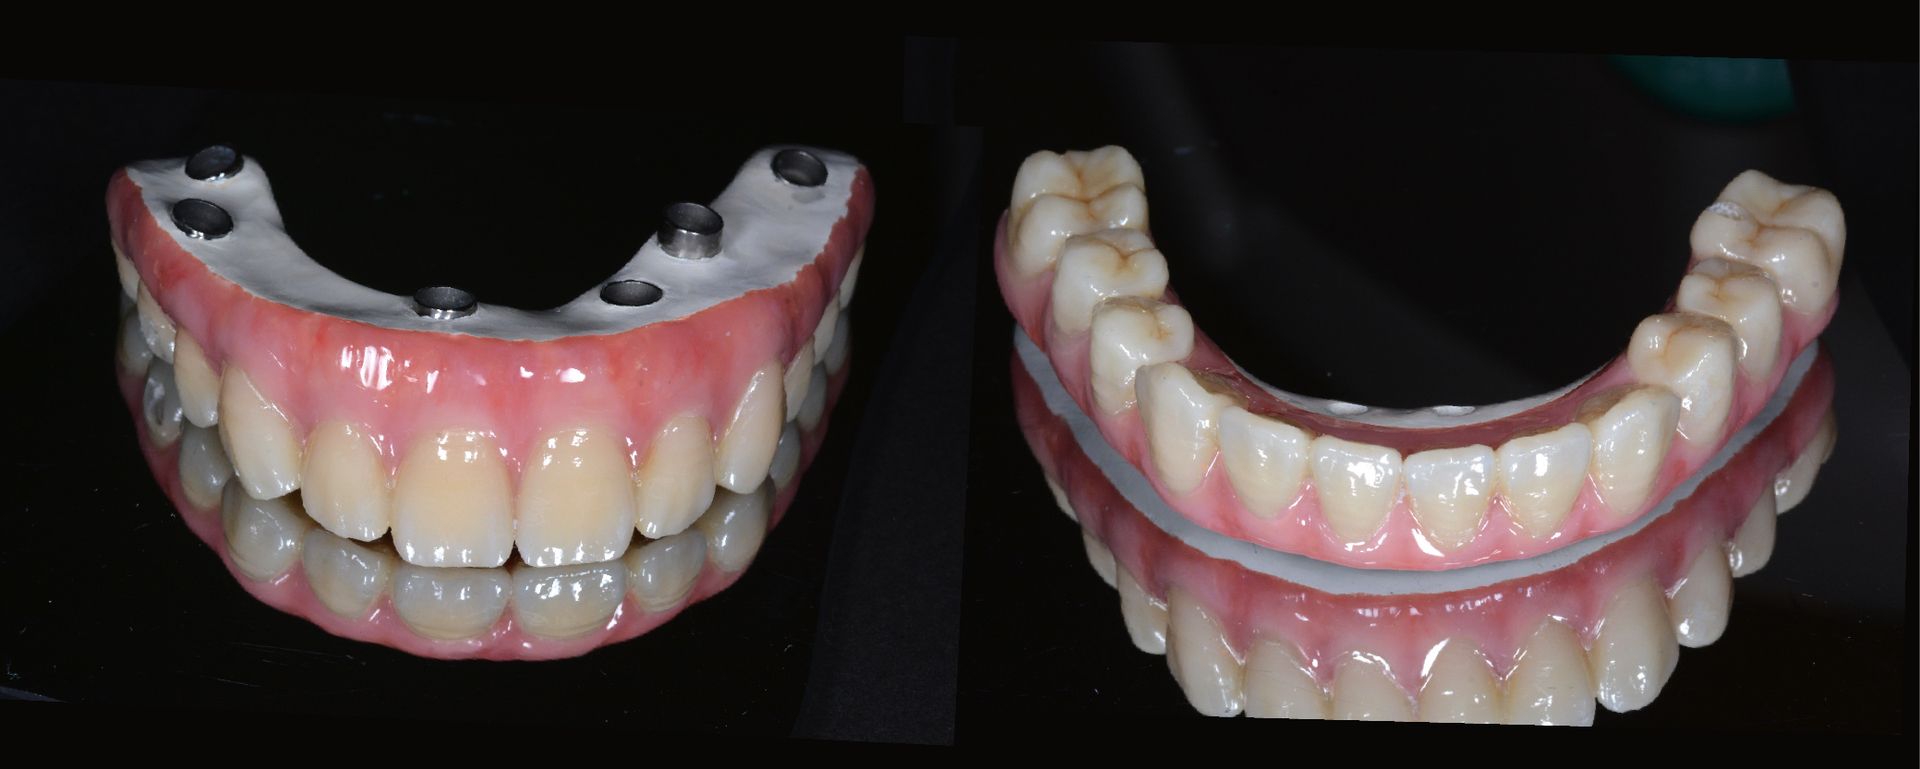

正式假牙完成,賴伯伯再次重拾自信的笑容,吃得開心,自然生活也跟著快樂起來。